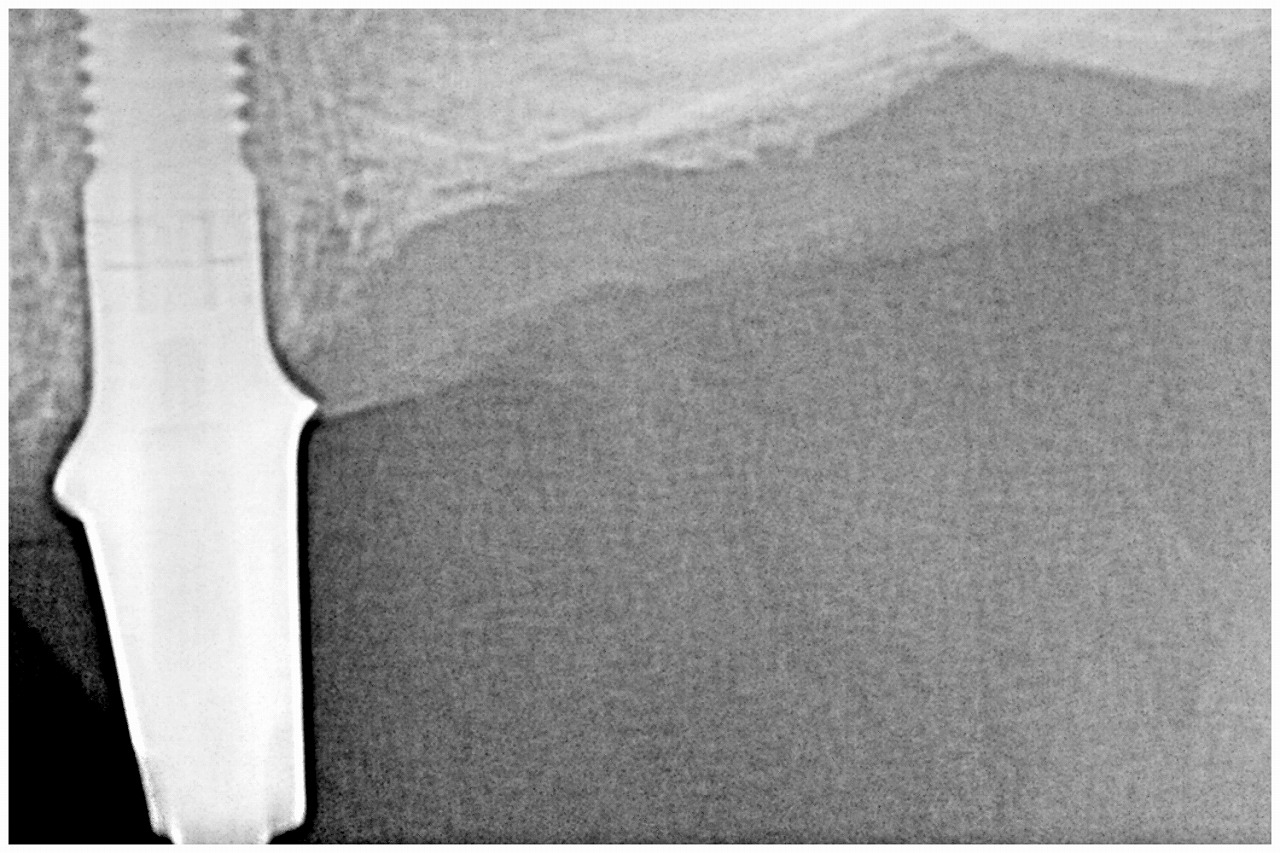

アバットメントが入りました

4番のインプラントになります

5番の傾斜埋入にインプラントになります